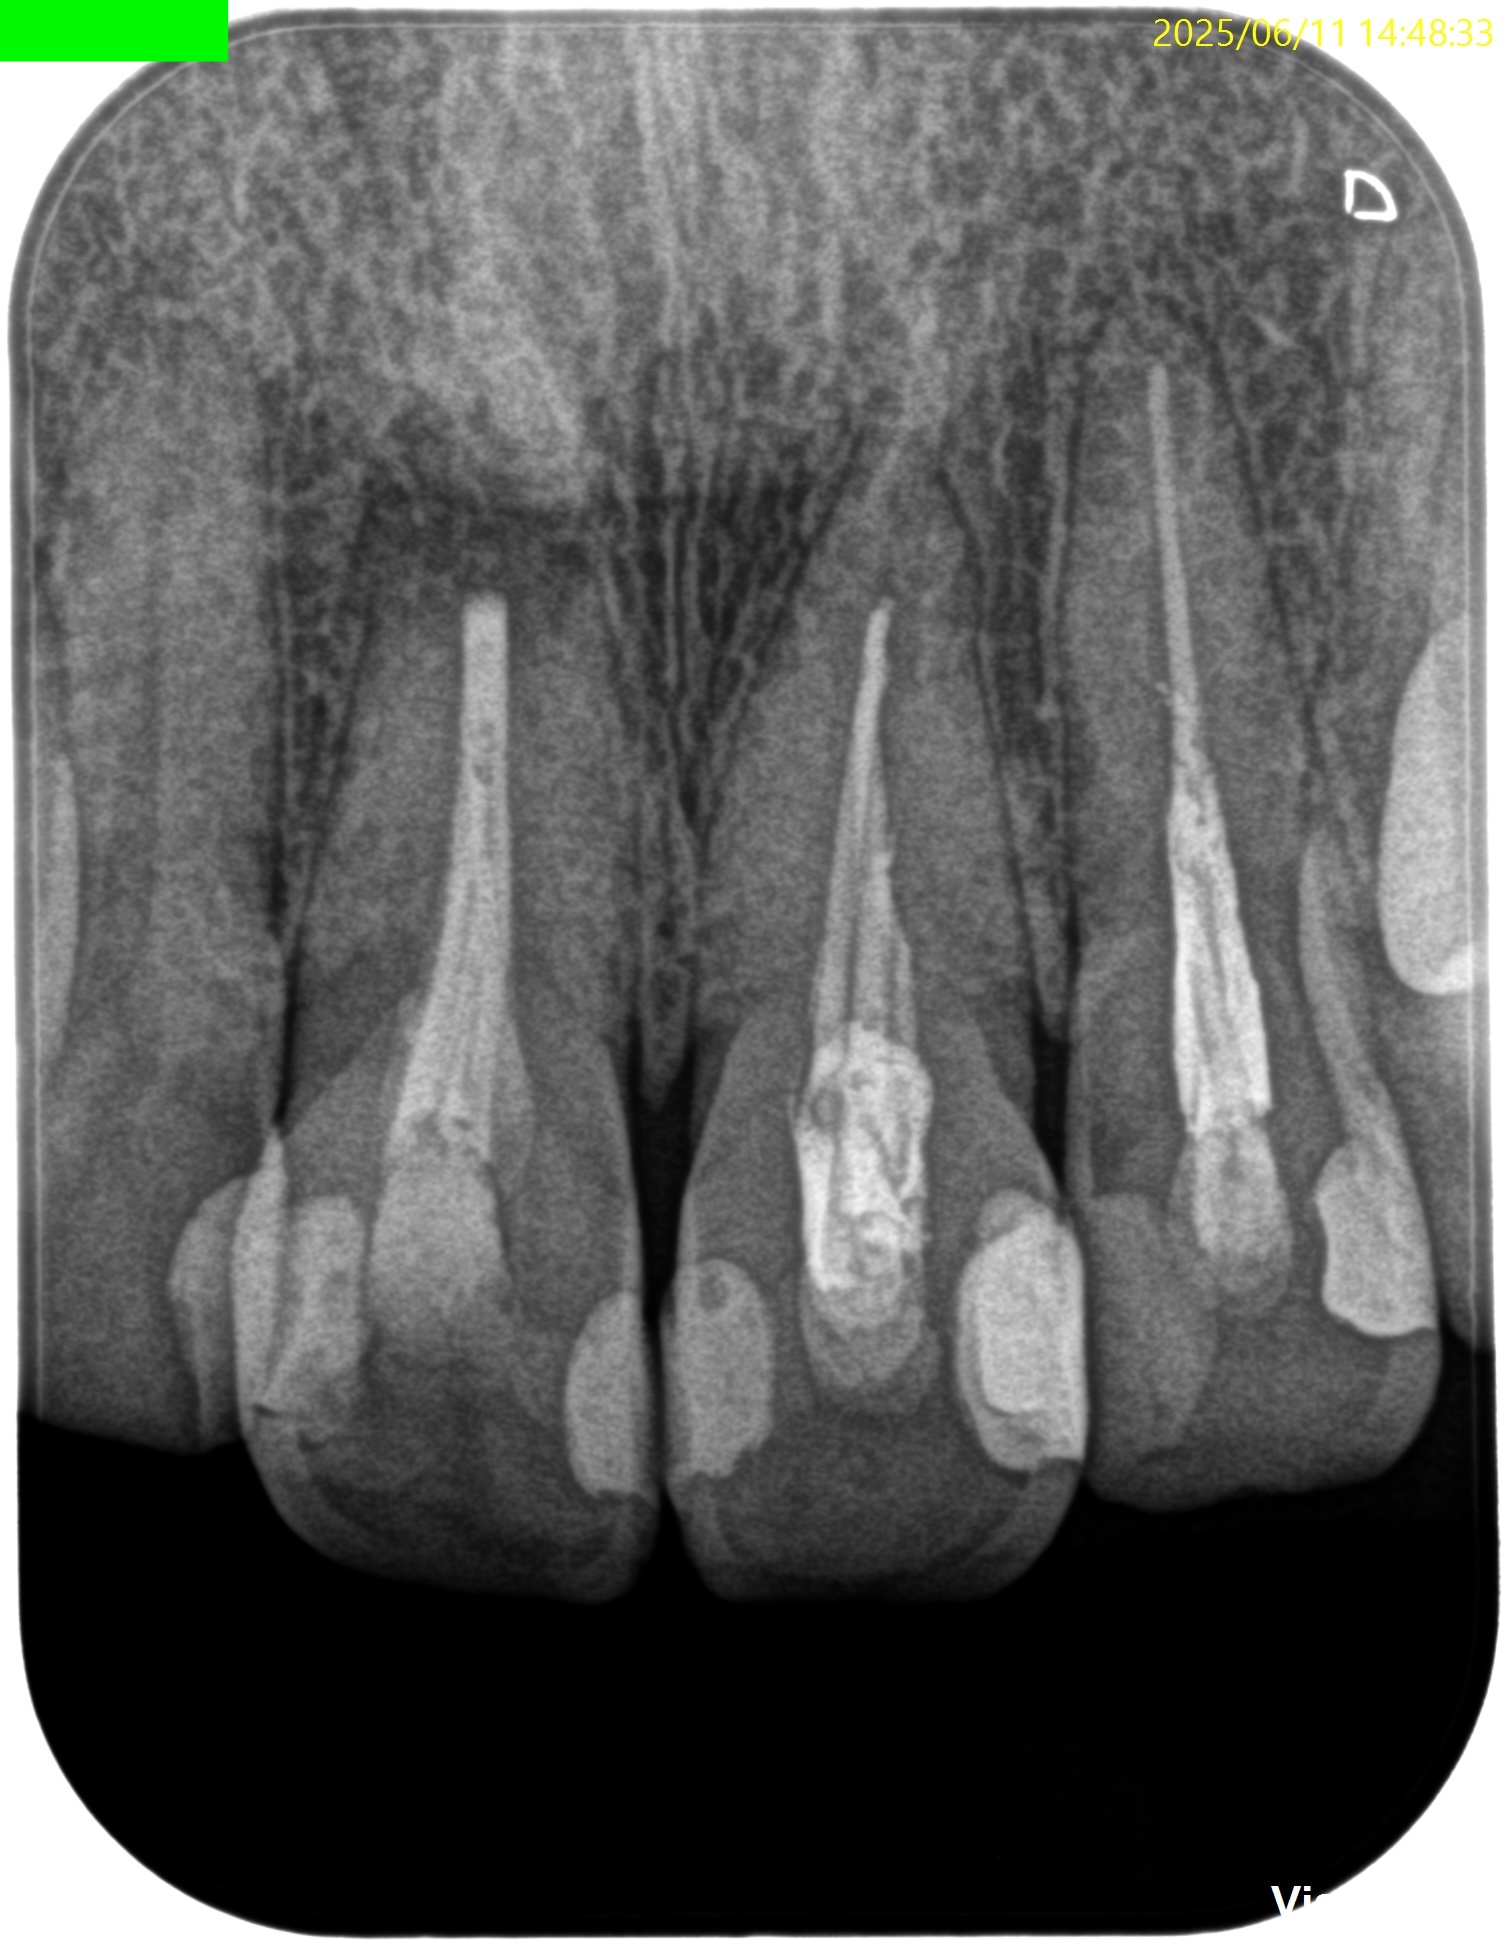

#8 Apicoectomy(2025.6.11)

PA, CBCTを撮影した。